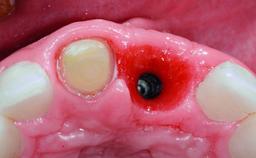

Replacement of a Missing Upper Left Central Incisor, Late Placement of an RC Bone Level Implant and Adjacent Tooth Restoration

A healthy 38-year-old male patient was referred for replacement of a failing tooth-supported cantilever fixed dental prosthesis on teeth 11 and 21. The patient reported a history of trauma at 13 years of age that had resulted in the subsequent loss of tooth 11, as well as endodontic treatment of the adjacent abutment tooth 21. A metal-ceramic cantilever fixed dental prosthesis replacing tooth 11 had been provided by his general dentist several years after the loss of the tooth, with tooth 21 as the sole abutment. At the time of initial presentation, this restoration had been in service for over 20 years.